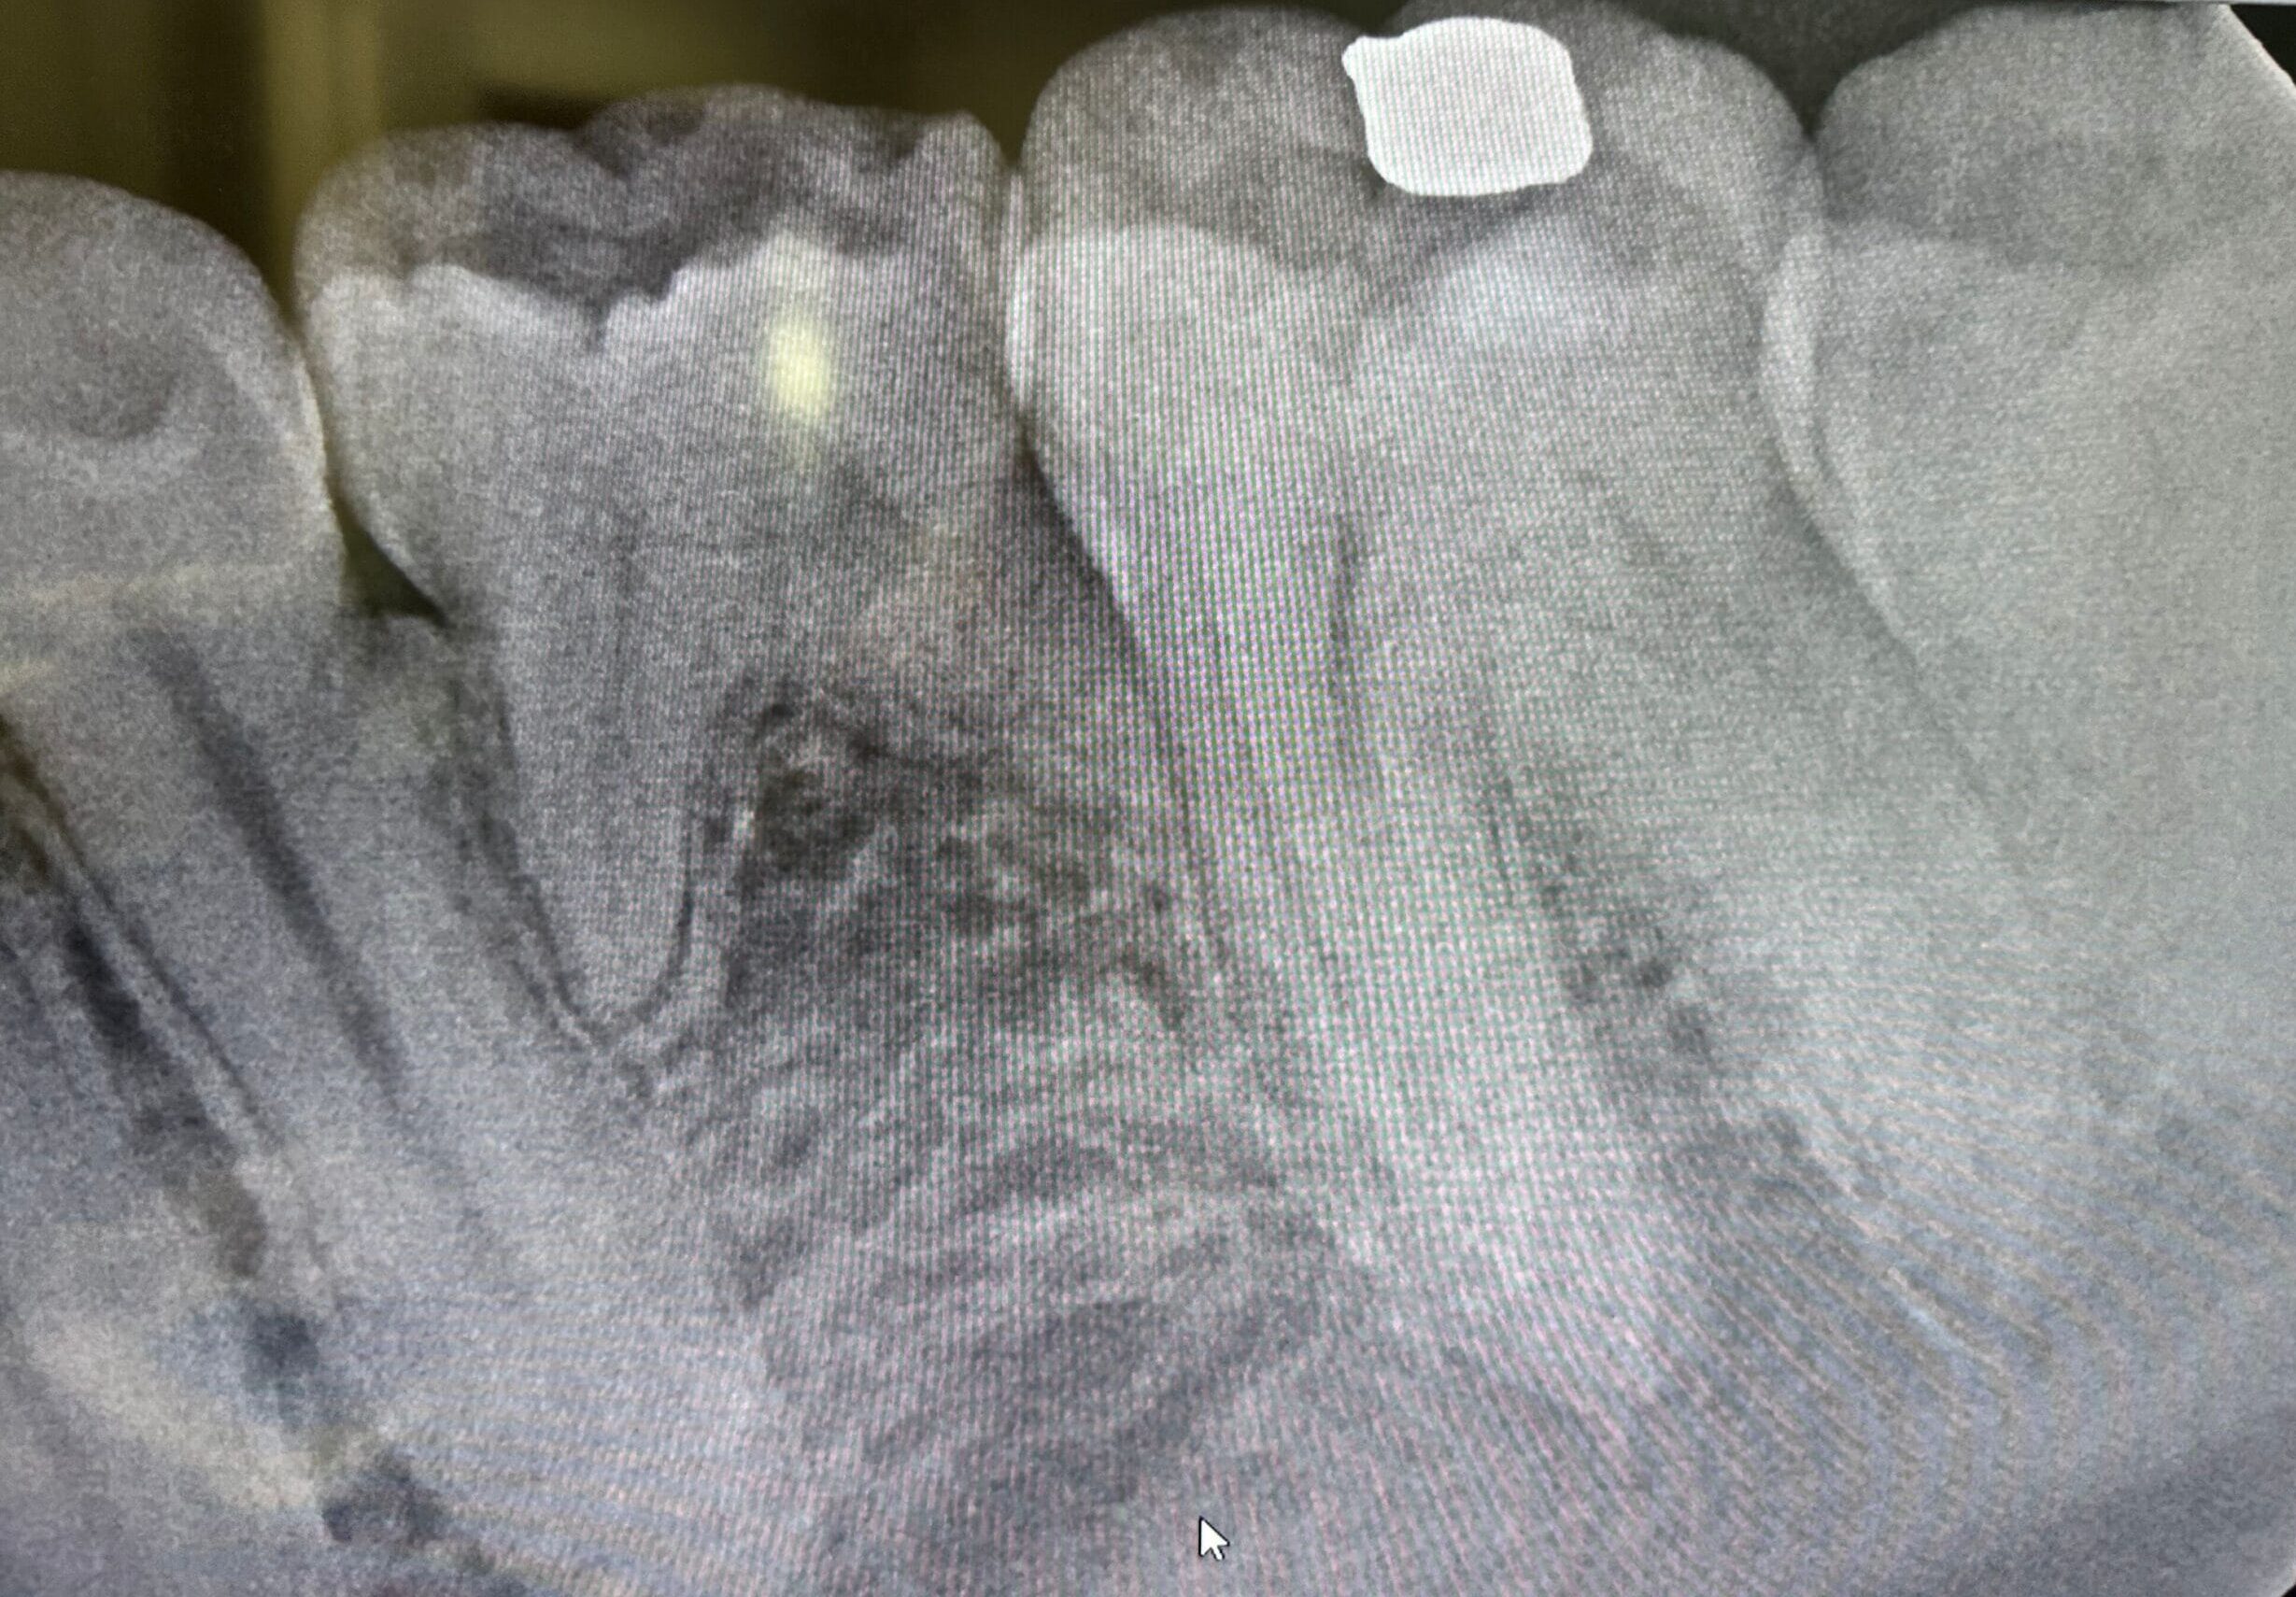

Dental X-rays (radiographs) are images that show the structures inside your mouth that aren’t visible during a regular dental exam. These images capture your teeth, the roots beneath your gums, and your jawbone, revealing potential issues like decay between teeth, bone loss, impacted teeth, abscesses, or cysts. Different types of X-rays serve various diagnostic purposes, ranging from detecting cavities to planning orthodontic treatment or dental implants.

Digital dental X-rays at MacPhail Signature Smiles reduce radiation exposure by up to 90% compared to traditional film X-rays while providing faster imaging without chemical film development. Our advanced digital sensors capture highly detailed images that appear instantly on our computer screens, allowing us to magnify, enhance, and analyze them with you right in the treatment room. Digital radiography significantly improves our diagnostic accuracy, leading to more timely and effective treatments while enabling better storage and quick retrieval of your dental records over time.

Interactive Results Review

Dr. MacPhail, DDS analyzes your X-ray images and shares findings with you on our high-definition chairside monitors, where you can see exactly what she sees. She points out important structures and explains any concerns using clear, non-technical language you can easily understand. These digital images become part of your secure electronic record, enabling precise comparison during future visits.